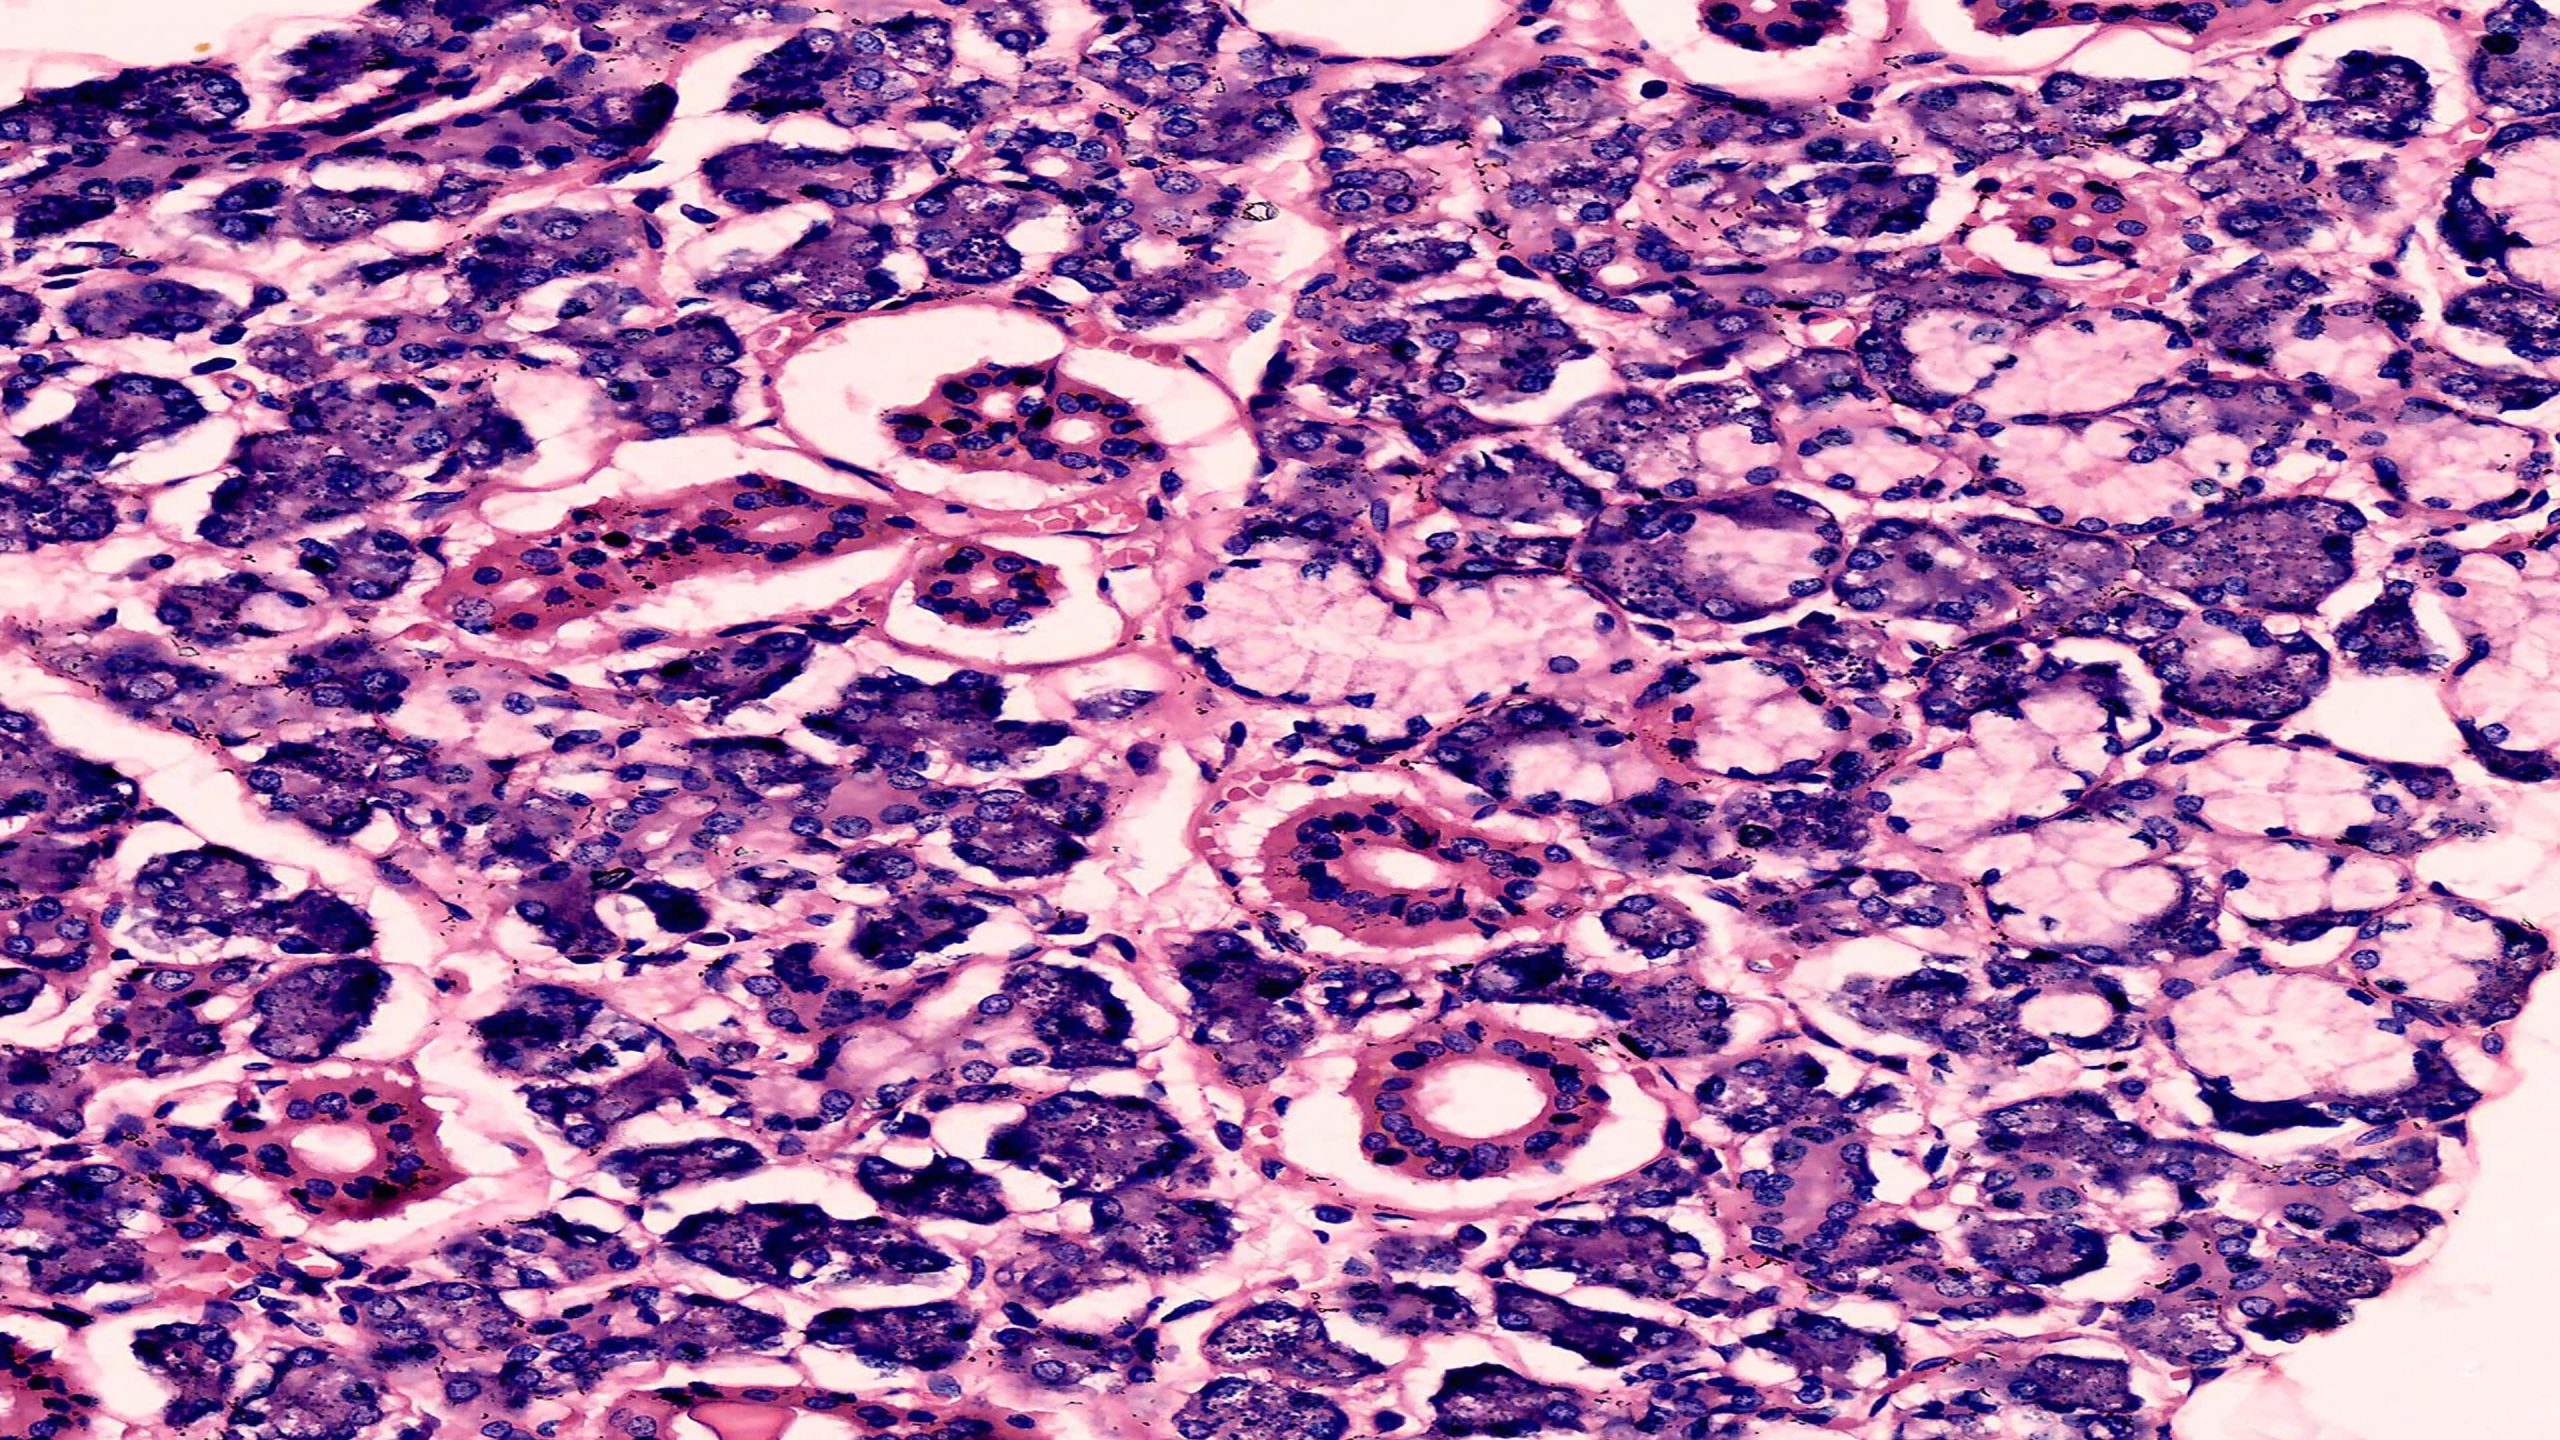

Mucous Salivary Gland 40X